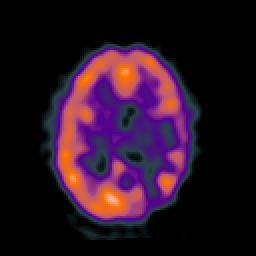

SPECT TC Study #6 -- Slice #33

[Home][Help][Clinical][Tour 1][Tour 2][Tour 3] Slice 33